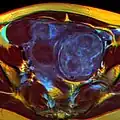

MRI image with multiple uterine leiomyomas